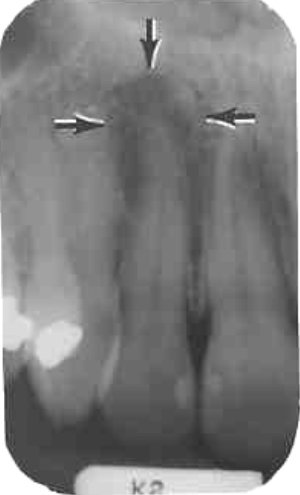

1. What is the anatomical structure indicated by the arrow in this radiograph?

2. What is the anatomical structure indicated by arrow in this radiograph?

3. What is the anatomical structure indicated by arrow in this radiograph?

4. What is the anatomical structure indicated by arrow in this radiograph?